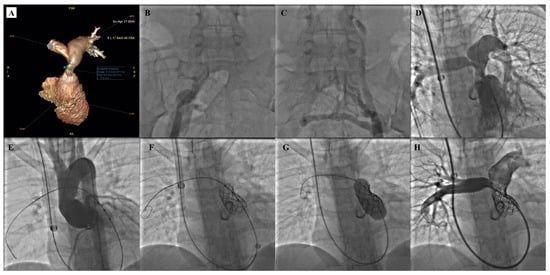

- Gillespie, M.J.; Benson, L.N.; Bergersen, L.; Bacha, E.A.; Cheatham, S.L.; Crean, A.M.; Eicken, A.; Ewert, P.; Geva, T.; Hellenbrand, W.E.; et al. Patient Selection Process for the Harmony Transcatheter Pulmonary Valve Early Feasibility Study. Am. J. Cardiol. 2017, 120, 1387–1392. [Google Scholar] [CrossRef] [PubMed]

- Gillespie, M.J.; Bergersen, L.; Benson, L.N.; Weng, S.; Cheatham, J.P. 5-year outcomes from the harmony native outflow tract early feasibility study. JACC Cardiovasc. Interv. 2021, 14, 816–817. [Google Scholar] [CrossRef]

- Gillespie, M.; McElhinney, D.; Jones, T.; Levi, D.; Weng, S.; Cheatham, J. Midterm outcomes from the harmony transcatheter pulmonary valve pivotal trial and continued access study. Pediatr. Cardiol. 2021, 42, 1903–1904. [Google Scholar]

- Levi, D.S.; Gillespie, M.J.; McElhinney, D.B.; Jones, T.K.; Benson, L.N.; Justino, H.; Haugan, D.; Cheatham, J.P. One-year outcomes in an expanded cohort of harmony transcatheter pulmonary valve recipients. J. Soc. Cardiovasc. Angiogr. Interv. 2022, 1, 100326–100327. [Google Scholar] [CrossRef]